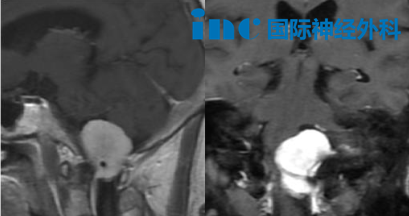

4月21日当天,他在北京天坛医院再次成功完成一台高难度的枕骨大孔区脑膜瘤手术。患者周女士60岁,脑膜瘤已对脑干下部和上段颈髓造成明显压迫。手术的核心在于充分显露病变、精准处理周围骨质,同时保护椎动脉和神经结构。操作步骤环环相扣、每一步都有严格的规范和顺序要求。这既是手术的主要挑战,也是巴教授数十年来持续钻研的技术要点。最终在巴教授与天坛医院国际部专家的配合下,肿瘤被顺利切除,术中未出现任何并发症。参与这台手术的天坛国际部专家也坦言:这台手术难度不小。

枕骨大孔位于颅骨底部,即头颅与颈椎的连接处。虽然颅骨看起来是一个完整的结构,但大脑的神经和血管必须与外界相连,因此在骨壁上预留了多个开口,枕骨大孔就是其中之一。这个孔道空间狭窄,却集中了大量维持生命活动的关键结构。

图:枕骨大孔区,从右背外侧和下角观察颅骨(a)和右背外侧颅骨区图示(b)。如大箭头所示,枕骨大孔前缘和神经轴前表面的直线视图被枕骨大孔外侧缘、髁状突后导管和寰枕关节内侧部分阻挡。通过部分磨除椎动脉硬脑膜入口正外侧的骨质结构,可以充分扩大手术视角,以便安全地操作神经轴的前外侧。OC:枕髁,JT:颈静脉结节。

手术的核心目标是在不额外损伤神经功能的前提下,解除对低位脑干和上颈髓的压迫。次要目标则包括维持寰枕关节的稳定性、减少对颅颈交界区肌肉的损伤、保护乙状窦和颈静脉球,以及避免空气栓塞或过度静脉出血。